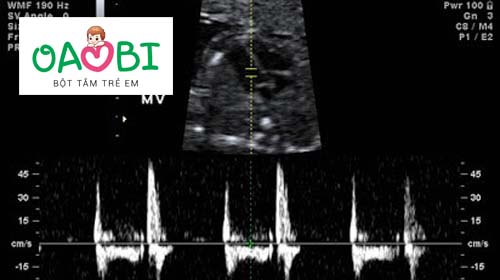

Cách chẩn đoán giới tinh thai nhi qua nhịp tim

Đoán giới tinh thai nhi qua nhịp tim là một trong những cách chẩn đoán khá hiệu quả và điều này cũng đã được các nhà khoa học chứng minh.